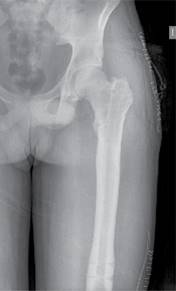

Se identificó el lugar de la osteotomía femoral siguiendo el método habitual descrito por Paley y colaboradores,13 realizándose mediante múltiples perforaciones a través de un abordaje lateral. Como describen algunos autores, estas perforaciones registran una baja tasa de tromboembolismo pulmonar.2 El punto de entrada del clavo se realizó en la punta del trocánter mayor a través de un abordaje lateral proximal (Figura 1), que permitió el fresado del canal femoral hasta 1.5-2 mm mayor que el diámetro definitivo del clavo seleccionado. Se introdujo el clavo intramedular Precice® hasta el borde proximal de la zona de osteotomía y se completó la misma a través del abordaje lateral, introduciendo el clavo hasta su localización definitiva y bloqueándolo proximal y distalmente (Figura 2). Por último, se realizó la distracción del clavo 1-2 mm para asegurar el correcto funcionamiento del dispositivo magnético.

Figura 1: Región de entrada para la introducción del clavo intramedular localizada en el trocánter mayor.